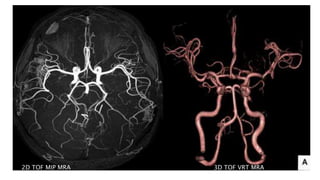

2D TOF MIP MRA 3D TOF VRT MRA

BILATERAL CAROTID MRA TOF MIP

LEFT ICA STENOSIS

and is recommended for screening

• #47 MR 2D ANGIO and 3D TOF MIP images show loss of flow related signals in right MCA. RIGHT ICA appear decreased in calibre as compared to left ICA

• #63 Here is TOF MIP and VRT MRA showing excellent angiogram due to background suppression and better flow related signal leading to better distal small vessel visibilty

• #64 here is an example of AP VIEW of normal MR angiogram of cervicocranial arterial system

• #65 In this MR angiography of bilateral carotid system there is e/o short segment narrowing of Left ICA s/o left ICA stenosis